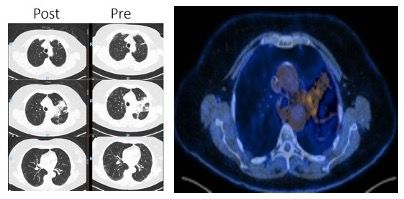

Three months after starting durvalumab, the patient developed a dry cough with no other symptoms. Physical examination was normal and oxygen saturation was 96%. The patient denied contact with coronavirus disease 2019 (COVID-19) positive patients and was practicing all measures of COVID-19 protection. A new PET-CT showed an excellent tumor response, with appearance of some ground-glass opacity in the lungs (Figure 6). A polymerase chain reaction (PCR) naso- and oropharyngeal test to detect severe acute respiratory syndrome (SARS) coronavirus 2 (SARS-CoV-2) was negative, as was the full respiratory viral panel. A subsequent durvalumab dose was put on hold to better define the diagnosis. After 48 hours, the patient repeated the SARS-CoV-2 test; the results were again negative. Due to the COVID-19 pandemic and her very good clinical status, the patient did not receive corticosteroids at this time and was instead monitored every 48 hours with telemedicine. The cough disappeared after 1 week and a new COVID-19 test was negative. Durvalumab was reinitiated 2 weeks later and the patient is still receiving the medication with no new symptoms, with a very good tolerance. After 3 months a new PET-CT (Figure 7) showed an almost complete resolution of the ground-glass opacity, and the patient maintains an excellent response.

Figure 6. PET-CT with an excellent tumor response and appearance of ground-glass opacity.

Figure 7. PET-CT with a tumor good response and resolution of almost all ground-glass opacity.